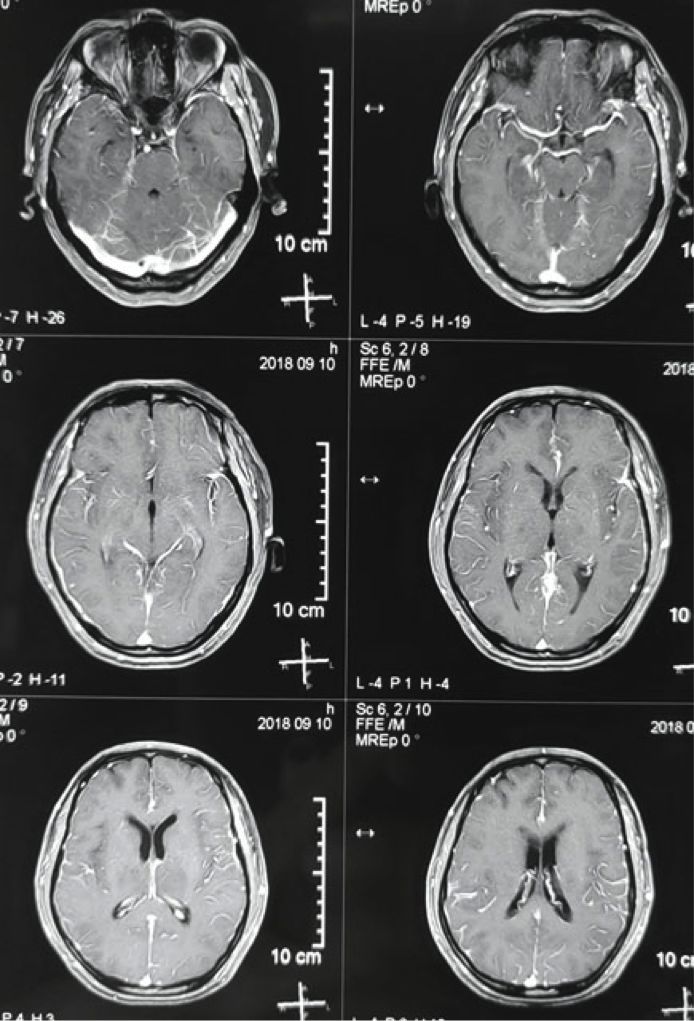

患者于2018年9月初开始出现间断头疼、失语、反应迟钝,并进行性加重,但头颅MRI(2018.09.10)脑实质未见明显转移,予以对症支持治疗。

图5. 2018年9月10日患者头颅MRI检查影像